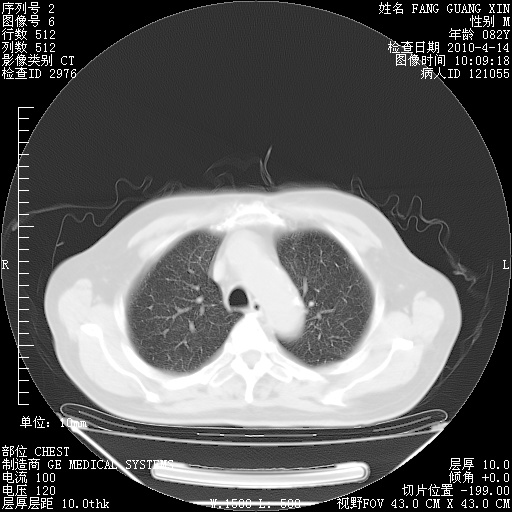

4月14日肺部CT

楼主| 发表于 2010-4-28 16:51 | 显示全部楼层

楼主| 发表于 2010-4-28 16:53 | 显示全部楼层

肺部CT平扫未见异常。